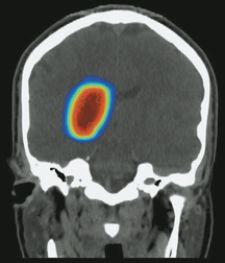

8) Proton Radiation. While most radiation beams harness their power from electrons, clinicians have started using protons to treat lung tumors. Because positively charged, subatomic protons only travel a limited distance through the body, proton radiation is thought to cause less damage to surrounding healthy tissue when compared to X-rays traditionally used in radiation therapy.

Proton-based radiation therapy is particularly useful for 4-D adaptive radiotherapy in treating lung cancer, where breathing can move the lung, making it difficult to hit the target. One obstacle to widespread adoption of proton radiation, however, is the need for an algorithm that quickly calculates the proton beam’s direction and intensity for each breathing phase.